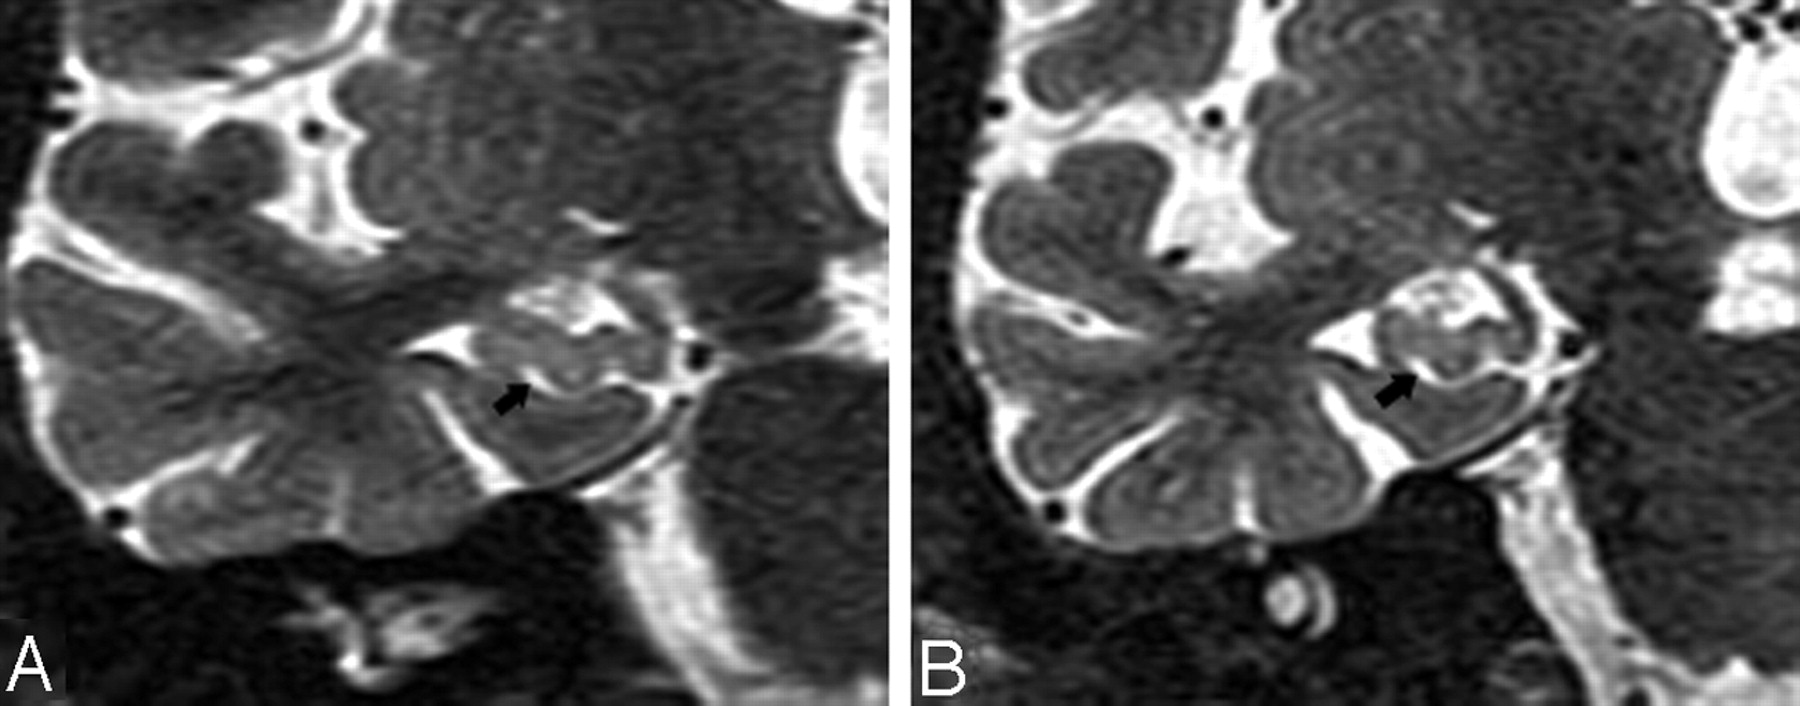

In the coronal plane, the differentiation of a HSC in the presence of a dilated uncal sulcus is challenging. As seen in Figs 4A and 5A, these CSF structures look very similar. They can be differentiated by identifying the medial to lateral course of the uncal sulcus through its continuation with the ambient cistern. This relationship is clearly seen in a 3-year follow-up, when the uncal sulcus, but not the HSC, changed over time (Figs 4B and 5B). In the axial plane, the differentiation of a HSC from the PHF and from uncal sulcus can be difficult (Figs 6A and 7A). Comparing them, the HSC is again the more lateral and distributed along the vestigial primary hippocampal sulcus. We conclude that the coronal plane (Figs 6B and 7B) is most helpful for distinguishing between them.

T2 short-τ inversion recovery (STIR) MR coronal image obtained from a 74-year-old male normal control (NC) patient. A, Arrowhead shows a small hippocampal sulcus residual cavity (HSC); arrow shows perihippocampal fissures (PHF) (uncal sulcus). B, 3-year follow-up scan. Comparing A and B, there is progressive dilation of the uncal sulcus (arrow), but no obvious change in the size of the HSC (arrowhead).

T2 short-τ inversion recovery (STIR) MR coronal image was obtained from a 73-year-old male normal control (NC) patient. Arrows show a dilated uncal sulcus and no hippocampal sulcus residual cavity (HSC). B, 3-year follow-up.

T2 short-τ inversion recovery (STIR) MR image was obtained from a 66-year-old female normal control (NC) patient.

A, Axial plane, arrowheads show the hippocampal sulcus residual cavity (HSC) and arrow shows the uncal sulcus. We can best differentiate them on the coronal plane.

Image obtained from a 90-year-old female normal control (NC) patient. Axial (A) and coronal (B) T2 short-τ inversion recovery (STIR) MR image show the perihippocampal fissures (PHF) (black arrows). This is also best seen along the coronal plane (B).